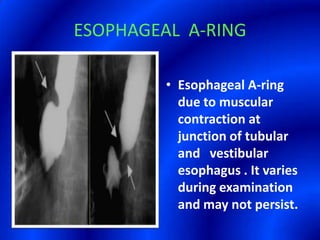

This document provides information about a barium swallow procedure. It begins with an introduction and overview of the embryology and anatomy of the pharynx and esophagus. It then describes the procedure itself, including preparation, technique, views obtained, and indications. Specific conditions that may be examined include pharyngeal and esophageal webs, foreign body impaction, scleroderma, dysphagia, mediastinal masses, and carcinoma. Diagrams are provided to illustrate normal anatomy and various pathological findings.